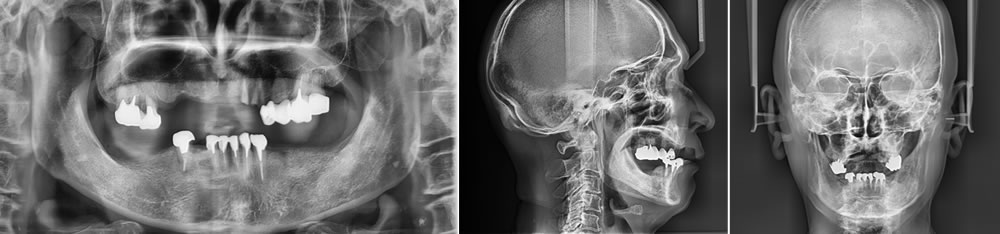

初診時の状態

残存している歯は全て不良補綴物の状態で、虫歯も進行していました。多数の欠損が認められ、すれ違い咬合という、上下の歯が噛み合う場所がなく、噛み合わせが非常に不安定な状態でした。

古い入れ歯を入れた状態では、修理を繰り返し、乱れた歯の状態で無理やり噛ませている事がわかります。

欠損も多数あり、口元の審美性は完全に失われた状態でした。

レントゲン検査により、保存不可能な歯が多数認められました。